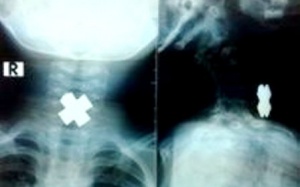

Dị vật hình chữ thập chắn ngang thực quản bé 3 tuổi

Trong lúc ông nội không để ý, cậu bé 3 tuổi đưa mảnh kim loại hình chữ thập vào miệng ngậm chơi. Bất ngờ mảnh kim loại trôi tuột xuống họng khiến cháu ho sặc, khó thở phải nhập...